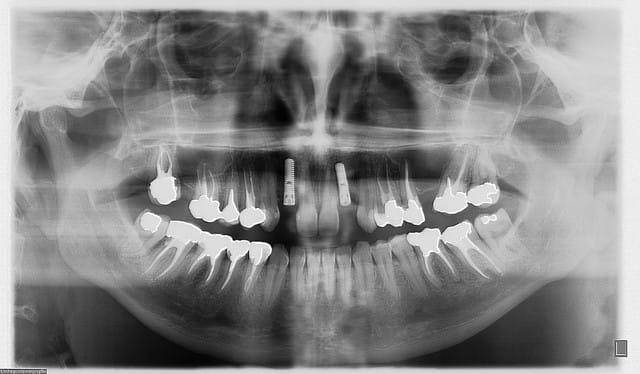

afin de dresser un tableau du cas...une petite présentation:

jeune femme de 35 ans, double agénésie des latérales sup, porte depuis la fin de l'adolescence un petit stellite de 2 dents...et n'en veux plus...

pas de problèmes de santé

budget assez serré...ne veux pas "d'interventions lourdes" (greffes)...et petit détail...un impératif de date...car elle se marie début juillet...

accepte un certain compromis esthétique (pour la concavité vestibulaire) car le sourire n'est pas gingival...d'où intervention avec expansion osseuse...

bon, première salve...

photos du scanner...et avec la planche radio pour bien estimer le volume disponible

d'entrée de jeu, on peut se dire que çà va être plus coton pour la 22 que pour la 12 car on à moins d'épaisseur et la corticale est plus dense...

pose de l'implant pas simple en effet pour la 22...la corticale m'a en effet "guidé" beaucoup plus en palatin que ce que j'aurais voulu (cf pano...on à presque l'impression que je suis dans la 21...mais c'est une déformation "optique" les 2 implants ont en effet la même longueur...13mm)

photos de l'empreinte d'étude pour les autres couronnes...photos de la prise de teinte...

je sais qu'il y a une petite différence de hauteur de collet...mais les implants étant pas mal enfouis (les vis de cicat font 3mm) une petite gingivoplastie s'impose pour la 12...

le gain en expansion n'est pas faramineux...mais quand même...